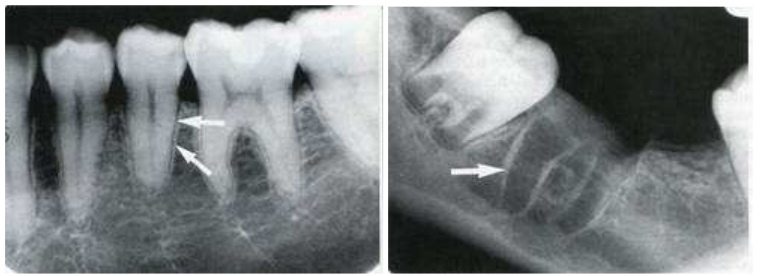

65.下圖根尖X光片中,白色箭頭所指為何構造?

(A)Periodontal ligament space (B)Alveolar crest (C)Cementum (D)Lamina dura

66.下圖中白色箭頭所指位於左下顎第二小臼齒根尖部位之放射線透過性(radiolucent)影像, 根據X光片影像中資訊判斷,下列何者最有可能?

(A)Apical granuloma (B)Radicular cyst (C)Dentoalveolar abscess (D)Mental foramen